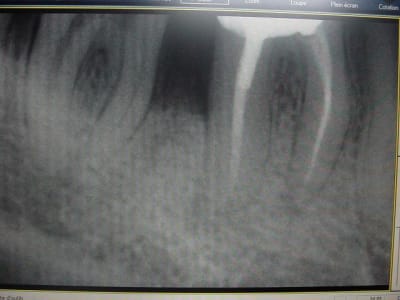

ci joint des retro de mars 2001 et aout 2003 de 46 qui montre l'evolution du cas..

bon, je suis loin d'etre d'acc avec vous consernant l'endo: regardez l'evolution de la lesion, de 2001 à 2003, sur les retro: il me semble très peu probable que l'endo ( pas top, ok mais d'apparence pas si tocarde) soit en cause. On voit en 2001 une atteinte distale, clairement paro.

En plus, problème endo sur 46, sur 35 et 17 qui engendrerais de telles lésion, c'est twilight zone! pour l'occlusion, je suis plus d'accord dans son role agravant important.